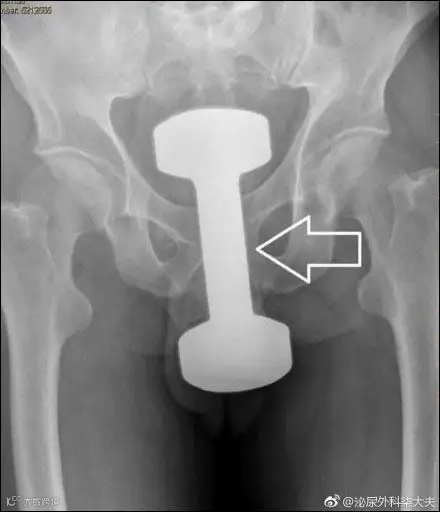

十斤重的哑铃▽